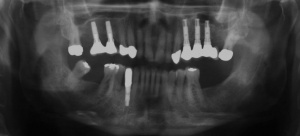

Der Erstbefund zeigte eine generalisiert entzündliche marginale Gingiva mit generalisierter Blutungsneigung bei Sondierung. Die approximalen Sondiertiefen waren durchgehend erhöht und betrugen im Molarenbereich bis zu 12 mm (s. Abb. 4). Es lagen multiple Zahnlockerungen vor, eine Zahnlockerung des Grades II zeigte sich an den Zähnen 11, 25, 26, 38, 37, 47; Grad III am Zahn 24. Harte Beläge in der Unterkieferfront, generalisiert weiche Beläge (API 62 %). Wurzelkaries an 24. Suffiziente Brückenversorgung im I. Quadranten. Die Panoramaschichtaufnahme von Juni 1998 (s. Abb. 4) zeigt einen generalisierten horizontalen Knochenabbau mit vertikalen Einbrüchen in regio 17, 25, 37 und 47. Interradikuläre Aufhellungen im Sinne einer Furkationsbeteiligung an 17, 26, 38, 37 und 47. Via falsa an 24.

Der Erstbefund vom 20.08.1998 zeigte eine lokalisiert entzündliche marginale Gingiva mit Blutungsneigung auf Sondierung (SBI 32 %) vorrangig in regio 17, 11, 21, 24, 27, 36, 37, 41, 46. Austritt von Pus aus der Tasche an 22. Die Sondiertiefen waren durchweg erhöht, an einzelnen Parodontien konnten bis zu 12 mm sondiert werden (s. Abb. 12). Generalisiert weiche Beläge (API 46 %), harte Beläge in der UK-Front. An 41 singuläre parodontale Rezession und Zahnlockerung des Grades II, hier auch sehr schmale keratinisierte Gingiva. Mobilitätstest und Blanchingtest positiv. Der Röntgenbefund der Panoramaschichtaufnahme vom 11.08.1999 (s. Abb. 13) zeigt einen generalisierten horizontalen Knochenabbau mit vertikalen Einbrüchen in regio 17, 24, 25, 26, 36, 41 und 47. Wurzelfüllung an 36. Konkremente sichtbar. 18 elongiert. 38 und 48 halbretiniert mit Aufhellung distal.